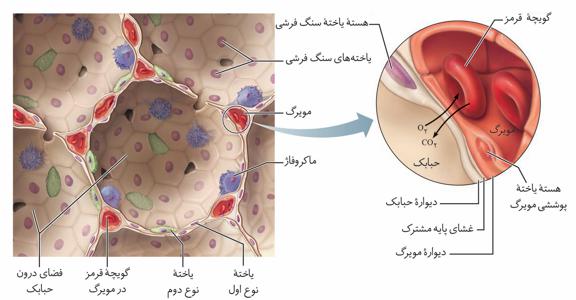

۱-کلافک(گلومرول) که درون کپسول بومن قرار دارد.

۲-دورِ لولهای که اطراف قسمتهای دیگر گُردیزه را فراگرفته است.

مویرگهای کلیه منفذدار هستند. پس ما هم کلافک و هم دور لولهای را منفذدار در نظر میگیریم.

به هر کلیه، یک سرخرگ وارد میشود. انشعابات این سرخرگ از فواصل بین هرمها عبور میکند و در بخش قشری به سرخرگهای کوچکتری تقسیم میشود. انشعاب انتهایی این سرخرگها، سرخرگ آوران نامیده میشود. سرخرگ آوران در کپسول بومن، شبکه مویرگی کلافک را میسازد. خون از طریق سرخرگ آوران به کلافک وارد میشود و از طریق سرخرگ وابران آن را ترک میکند.

گزینه «۲»: مطابق شکل کتاب درسی، دیواره بیرونی کپسول بومن شامل یاختههای سنگفرشی و غشای پایه آنهاست.

گزینه «۳»: مویرگهای کلیه از نوع منفذدار هستند.